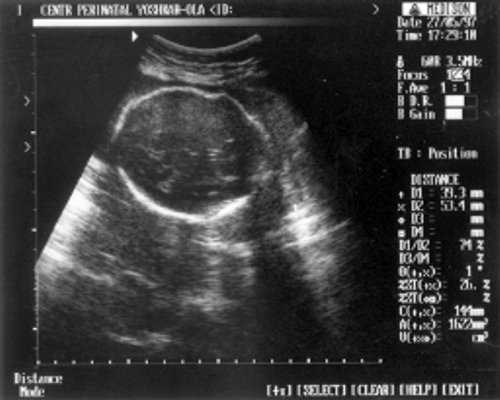

МРМ (межполушарный размер мозжечка) = 25,6 мм - 23,5-24 нед. (рис. 1)

- МРМ (межполушарный размер мозжечка) = 25,6 мм - 23,5-24 нед. (рис. 1)

Рис. 1. УЗИ плода - голова.